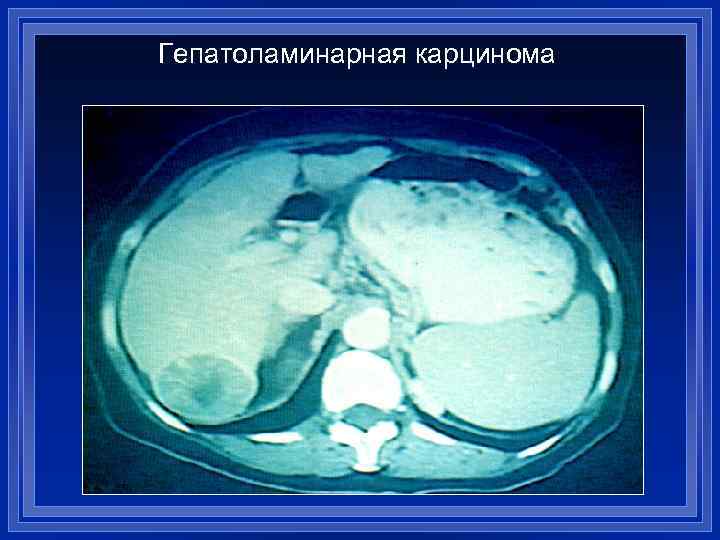

Гепатоламинарная карцинома